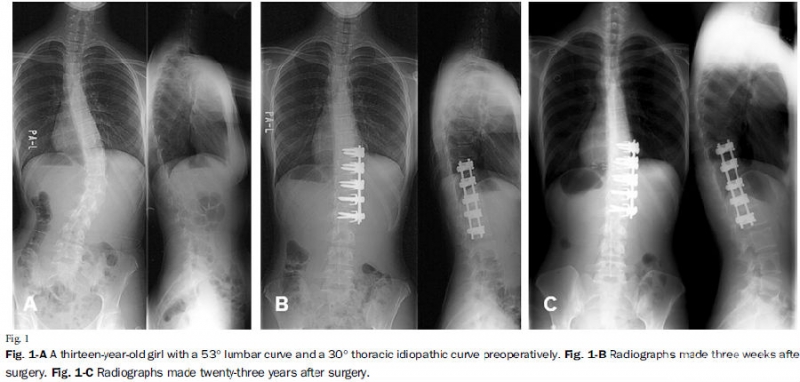

图7. Lenke 5C型AIS患者前路术后矫正效果满意,随访23年无明显进展